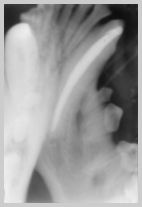

The apex of this 304 canine has

been missed due to incorrect angulation